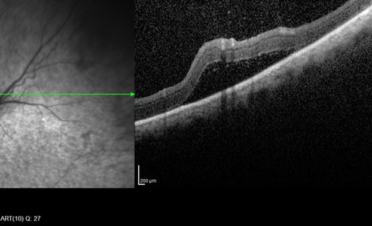

Haremos una OCT del segmento posterior cuando necesitemos:

- Medir las diferentes capas de fibras de la retina y el nervio óptico. Con este tipo de OCT realizamos un corte histológico en vivo de las diferentes capas del fondo ocular: retina, nervio óptico y coroides pudiendo llegar incluso hasta la esclerótica.

- Valorar cambios en la estructura, como por la presencia de exudados, hemorragias, degeneraciones,

edema, membranas epirretinianas, anomalías del vítreo posterior ….